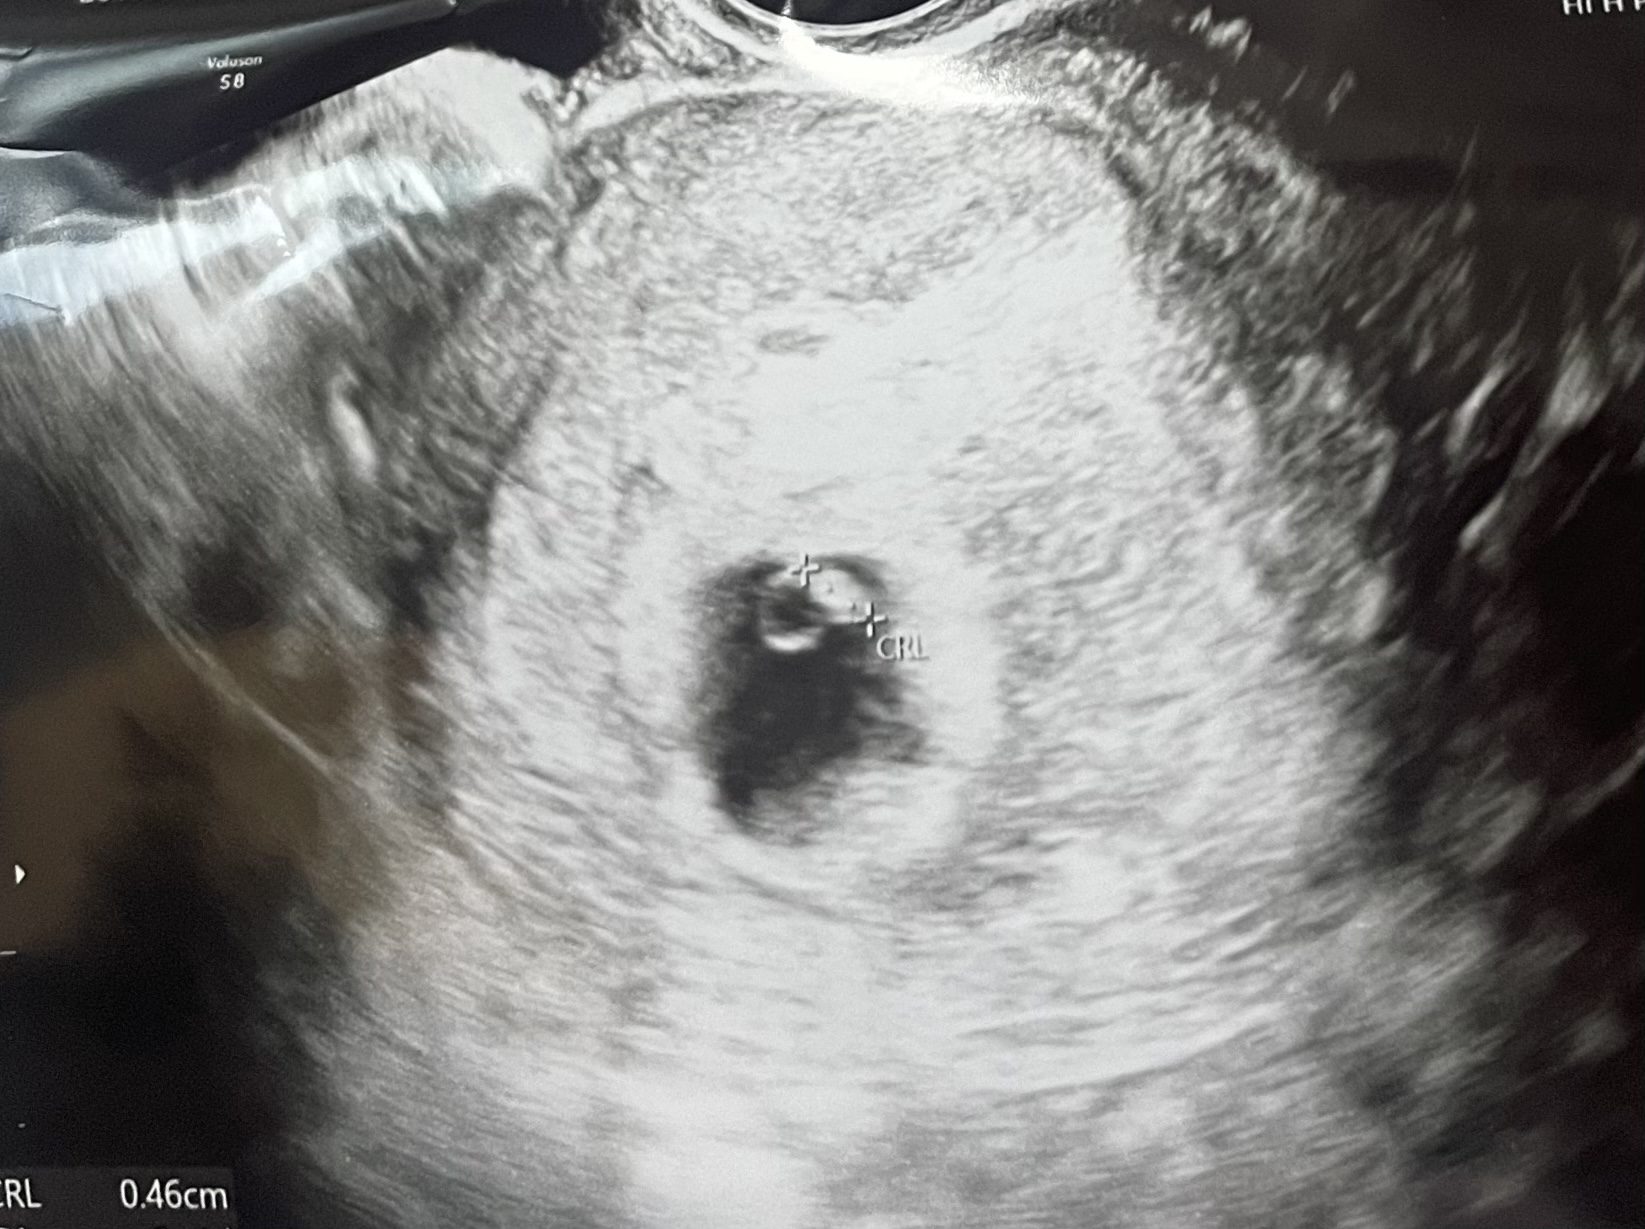

늦었다고 느꼈을 때, 가장 빠르게 찾아온 기적 - 희망나눔